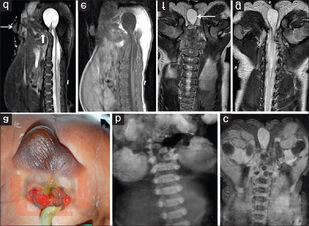

В предлагаемом учебном пособии представлены вопросы эмбриогенеза, классификации, диагностики и способы современного хирургического лечения аноректальных пороков развития у детей.